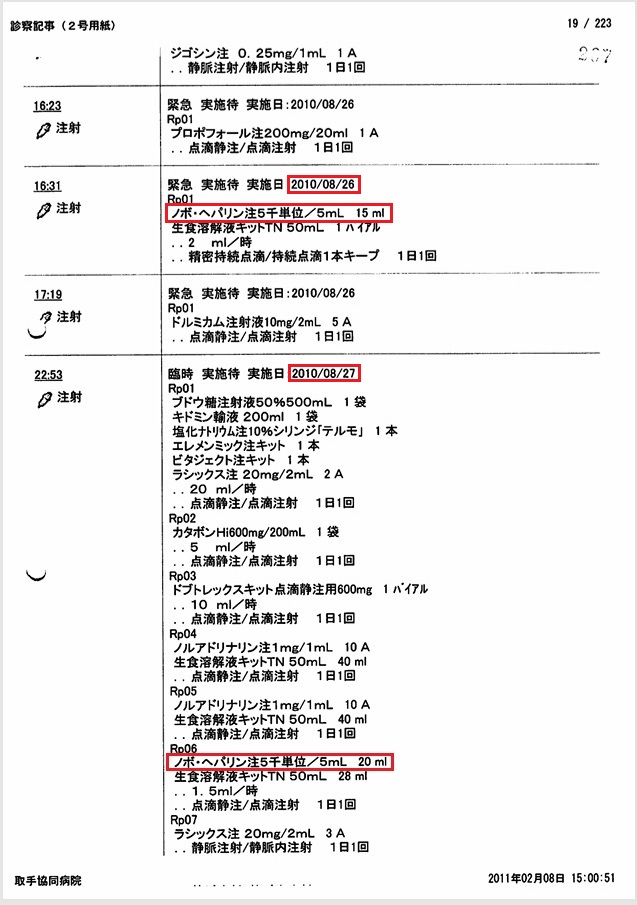

- 8月27日:APTT 92秒でヘパリン増量(死期を故意に早めようとした疑い)

胸腔、心嚢内への出血によるショックの進行中、8月27日の血液検査でAPTT 92秒とパニック値にもかかわらず、ヘパリンを15000単位から20000単位に増量。故意に死期を早めようとした疑い。

証拠:血液検査・注射処方箋の抜粋(赤枠部分)

8月27日の午後3時の時点で、血圧60/40 mmHg, 心拍数150~160/min、8時間尿量4mlと、いつ心肺停止してもおかしくない状態であった。 しかし医師は父がショックに陥った原因を「元々の心筋梗塞が重症のため」と偽り、 医療事故とそれに起因する緊張性血胸・心タンポナーデ、出血性ショックを隠蔽した。 またヘパリン15000単位/日が投与されていたが、この日の血液検査でAPTT 92秒とヘパリン投与量が過剰であったにもかかわらず、ヘパリンが20000単位/日に増量されており、故意に死期を早めようとした疑いがある。